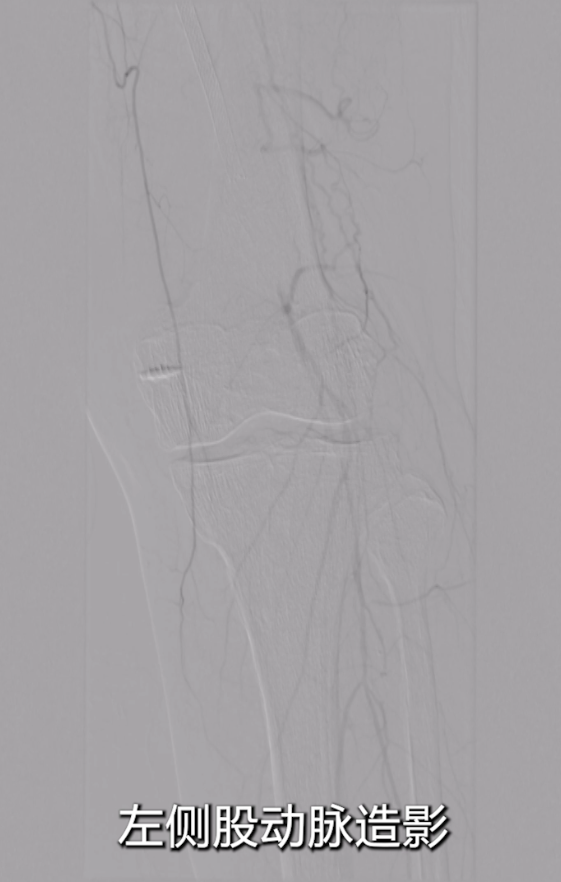

初步扩张:使用4×150mmSterling球囊,由近及远扩张整个支架段及远端病变(考虑合并P1段病理性改变);

在影像图下发现在在支架远端有一定的局部狭窄。

药物球囊扩张后造影显示:支架远端(临近P2段)存在局部狭窄,使用5×150mmIris球囊对病变段再次预扩;

扩张后出现小夹层,血流速度仍较慢,采用4×80mmIris球囊对病变段再次预扩